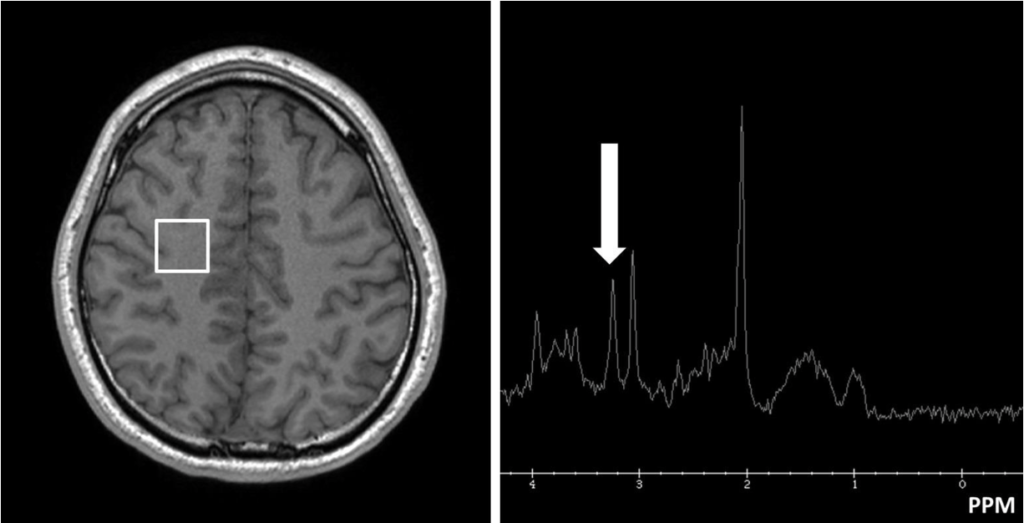

健常成人の脳(図左が関心領域)の1H-MRS スペクトラム(TR 2000 ms, TE 35 ms)を示す。矢印が示すピークの代謝物はどれか。

- Lactate

- Myo-inositol

- N-acetyl aspartate

- Creatine and phosphocreatine

- Choline-containing compounds

解説

- 間違い Lac: 1.3[ppm]

- 間違い ml: 3.5[ppm]

- 間違い NAA: 2.0[ppm]

- 間違い Cr: 3.0, 3.9[ppm]

- 正しい Cho: 3.2[ppm]